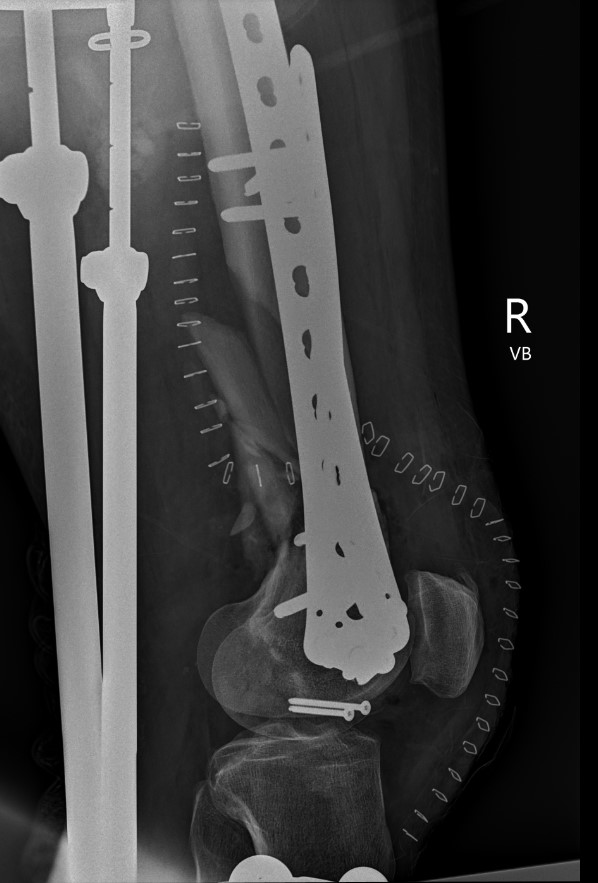

Type C: Complete articular

Xray / CT

Options

Dual Plate

Plate + Retrograde nail

Indications

Significant comminution

Loss of medial cortical buttress